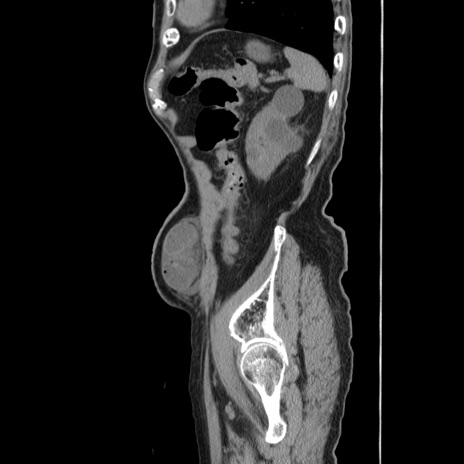

症例24(矢状断像)

【症例】80歳代男性

【主訴】左側腹部痛、嘔吐

【現病歴】本日早朝より左腹部に痛みあり。昼頃嘔吐認めたため、救急要請。

【既往歴】直腸癌(Mile手術)、胆摘

【身体所見】意識清明、BT 35.9℃、BP 221/93mmHg、SpO2 97%(RA) 、腹部:左ストーマ周囲に限局性の腹部膨隆あり。 膨隆部自発痛・圧痛あり・軟。

【データ】WBC 7700、CRP 0.09